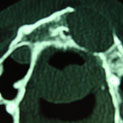

Aunque su estirpe anatomopatológica sea benigna, son quistes que en algunos pacientes provocan grandes destrucciones maxilares, porque crecen de forma asintomática durante años.

Su cirugía es sencilla y está basada en la extracción del quiste con criterios conservadores, y en la reconstrucción del defecto creado por la limpieza quirúrgica.

Para la reconstrucción, aconsejamos hacerlo en la misma intervención y con las bases de ingeniería tisular de la regeneración ósea guiada. Utilizamos como material óseo inductor el fosfato tricálcico tipo beta, mezclado con sangre del paciente y protegido con membrana de regeneración reabsorbible.